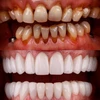

Zirkonyum uygulamalar

Porselen uygulamaları

Laminate veneer